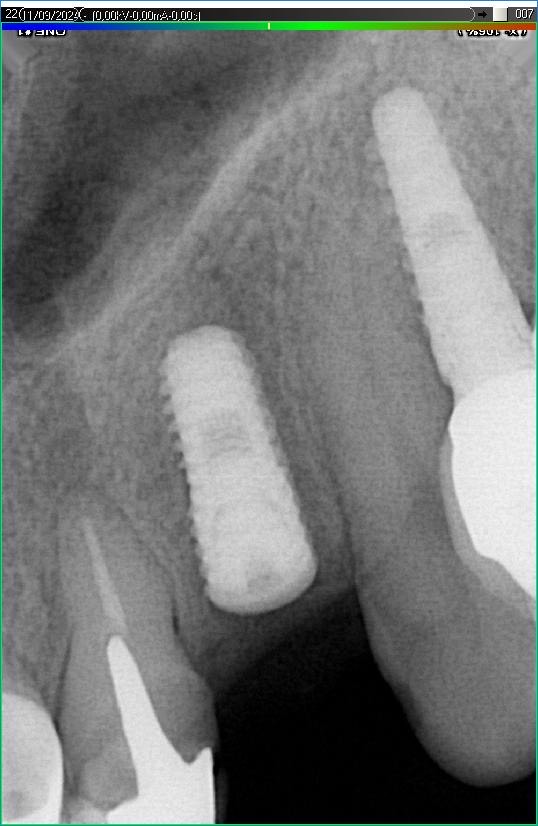

Імплантація